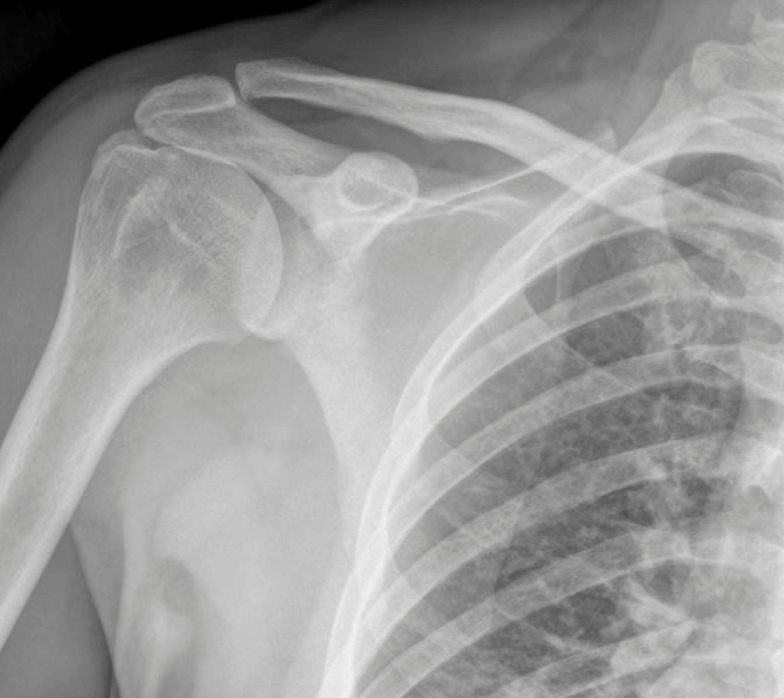

more »Understanding the skeletal system

A foundation for physiotherapy and your health When it comes to your health, your bones are the backbone – literally! Keeping your bones healthy is essential to prevent pain, injury, and long-term issues. That’s where we come in. If you feel like your ol’ bones are aching (especially if you’re young) call us on 9729 […]